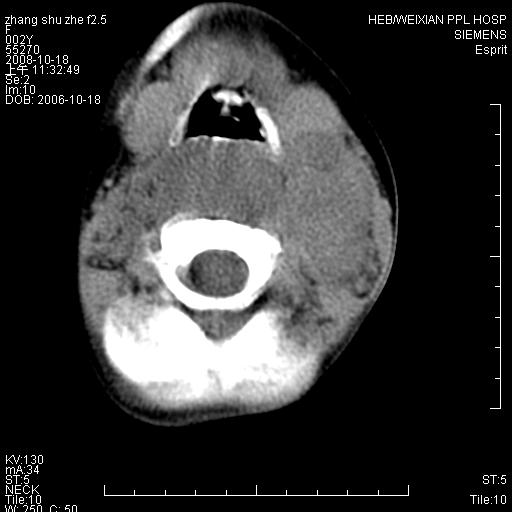

以下是引用dyqct在2009-2-10 21:04:00的发言:[br]年龄?性别?有发烧吗?[br]鼻咽部、口咽部、喉咽部及颈椎前间隙广泛肿厚,明显占位效应并致相应组织变形。ct值22-28hu。[br]考虑:1、颈前脓肿可能性大;[br] 2、建议增强或治疗后复查。

以下是引用jiangjing在2009-2-11 11:37:00的发言:[br]急性病程,鼻咽部、口咽部、喉咽部及颈椎前间隙广泛肿厚,明显占位效应并致相应组织变形.考虑颈部感染性病变(脓肿?);建议行进一步检查。